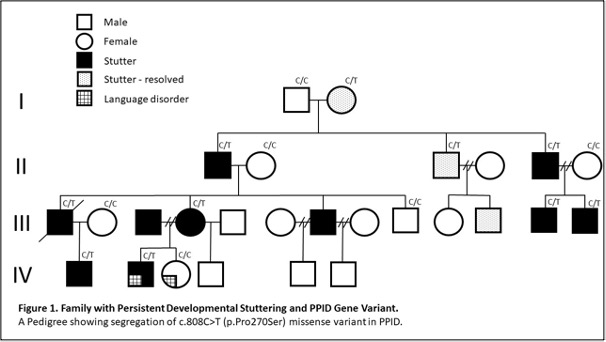

| Family with Persistent Developmental stuttering and PPID Gene Variant. A Pedigree showing segregation of c.808C>T (p.Pro270Ser) missense variant in PPID. |

In research published in the journal Brain, we studied 27 members of a four-generation Australian family; ten members of this family have stuttering and three used to have stuttering but this was resolved in adulthood after therapy.

We also found a variant of a newly discovered gene called PPID in the family members with severe developmental stuttering. PPID codes for a chaperone protein, and so for the first time we have a link between stuttering and a ‘chaperone pathway.’

We have known for some time that there is a genetic link to stuttering, but this study is the first to show that genetic changes passed on in families can alter brain development leading to structural anomalies that underly stuttering.